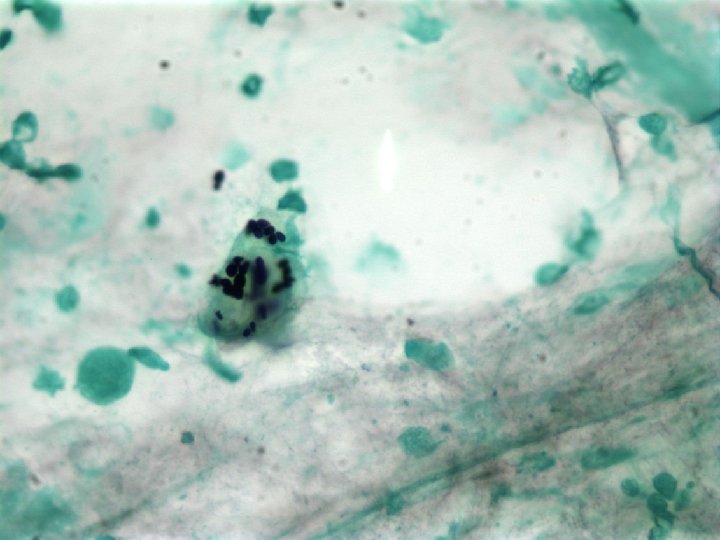

Diagnosis • Culture – Several weeks for growth – DNA probe – Exoantigen test • Histopathology – Budding yeast within macrophages or free in tissue • Antigen Tests – Urine or blood • Antibody Tests – Complement fixation – Immunodiffusion